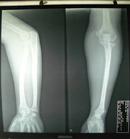

常規X線平片檢查時,可以發現掌指關節和近側指間關節的關節下有囊腫形成、骨侵蝕、關節間隙狹窄和骨贅形成,在腕骨和下尺橈關節亦有囊腫形成和侵蝕,少數遠側指間關節也可有變化。關節下囊腫最早出現,通常位於關節近側,常見的是掌骨頭部的關節下區有直徑1~3mm的圓形或卵圓形的小囊腫,周邊有界限清晰的硬化區。隨後出現關節間隙狹窄和骨贅形成,關節間隙狹窄不均勻,在關節受侵蝕處最為明顯。但關節間隙狹窄並不一定與囊腫形成相一致,有時可有數個關節下囊腫形成而無關節間隙狹窄;也可以有明顯的關節間隙狹窄而無囊腫形成。骨贅形成一般是關節嚴重受累的表現,但並不一定伴有明顯的關節間隙狹窄,腕骨內可有邊界清晰的囊腫,其直徑5~6mm,常為多發性;同一骨內也可有2~3個囊腫,常見於頭狀骨、鉤骨、舟骨和月骨 部分患者的遠端尺橈關節和尺骨遠端也可能有改變。在尺骨遠端和莖突處可有數處囊腫和骨侵蝕。少數病例可在該關節的橈側出現囊腫,甚至在三角韌帶處顯示混濁陰影。

在膝、髖等較大關節的X線表現主要是軟骨混濁,此乃由於軟骨鈣化或鐵質沉積之故。